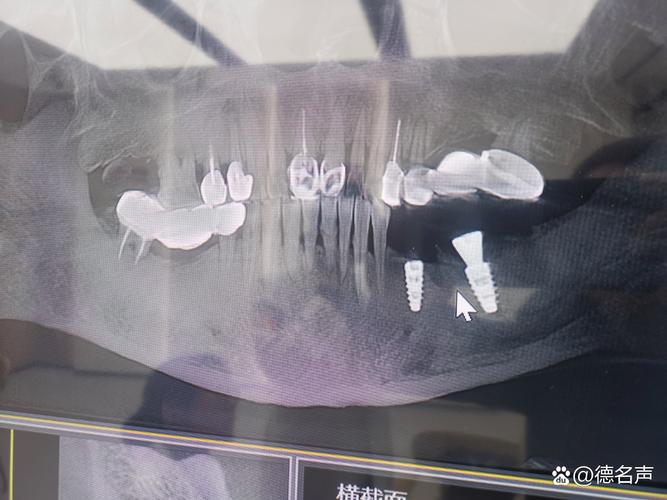

- 骨密度与骨量检测:采用双能X线吸收法(DXA)检测腰椎或髋部骨密度,明确骨质疏松程度(T值≥-1.0SD为正常,-1.0~-2.5SD为骨量减少,≤-2.5SD为骨质疏松);通过锥形束CT(CBCT)评估牙槽骨的骨量(高度、宽度)及骨密度(可通过Hounsfield值定量分析,骨密度值越低,骨质量越差)。

- 定期复查:术后1、3、6个月复查种植体稳定性与骨结合情况,之后每年复查一次,通过CBCT观察种植体周围骨密度与骨吸收情况,及时发现并处理并发症。